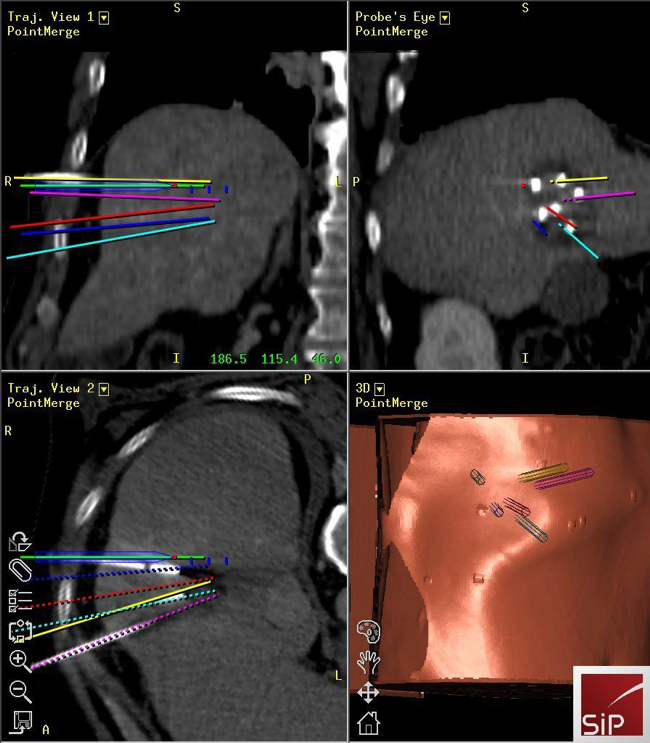

Interventional Oncology

Reto Bale

• Image-guided tumour ablation

• Stereotaxis

• Robotics

• Targeting

• Interventional oncology

Stereotactic ablation of liver tumours:

Radiofrequency ablation (RFA) allows local curative tumour treatment by inducing coagulation necrosis with a high-frequency alternating current. The major limiting factor of conventional US- and CT- guided percutaneous single probe ablation is the tumour size. Navigation systems allow for 3D-planning of multiple overlapping ablation zones on the CT datasets and precise transformation into the real patient. We developed the worldwide first aiming device for frameless stereotactic punctures and performed the first in man stereotactic radiofrequency ablation (SRFA) of a liver tumor in 2001. Meanwhile > 1000 patients with > 3000 liver tumors, most of them being inoperable, have successfully been treated at our department.